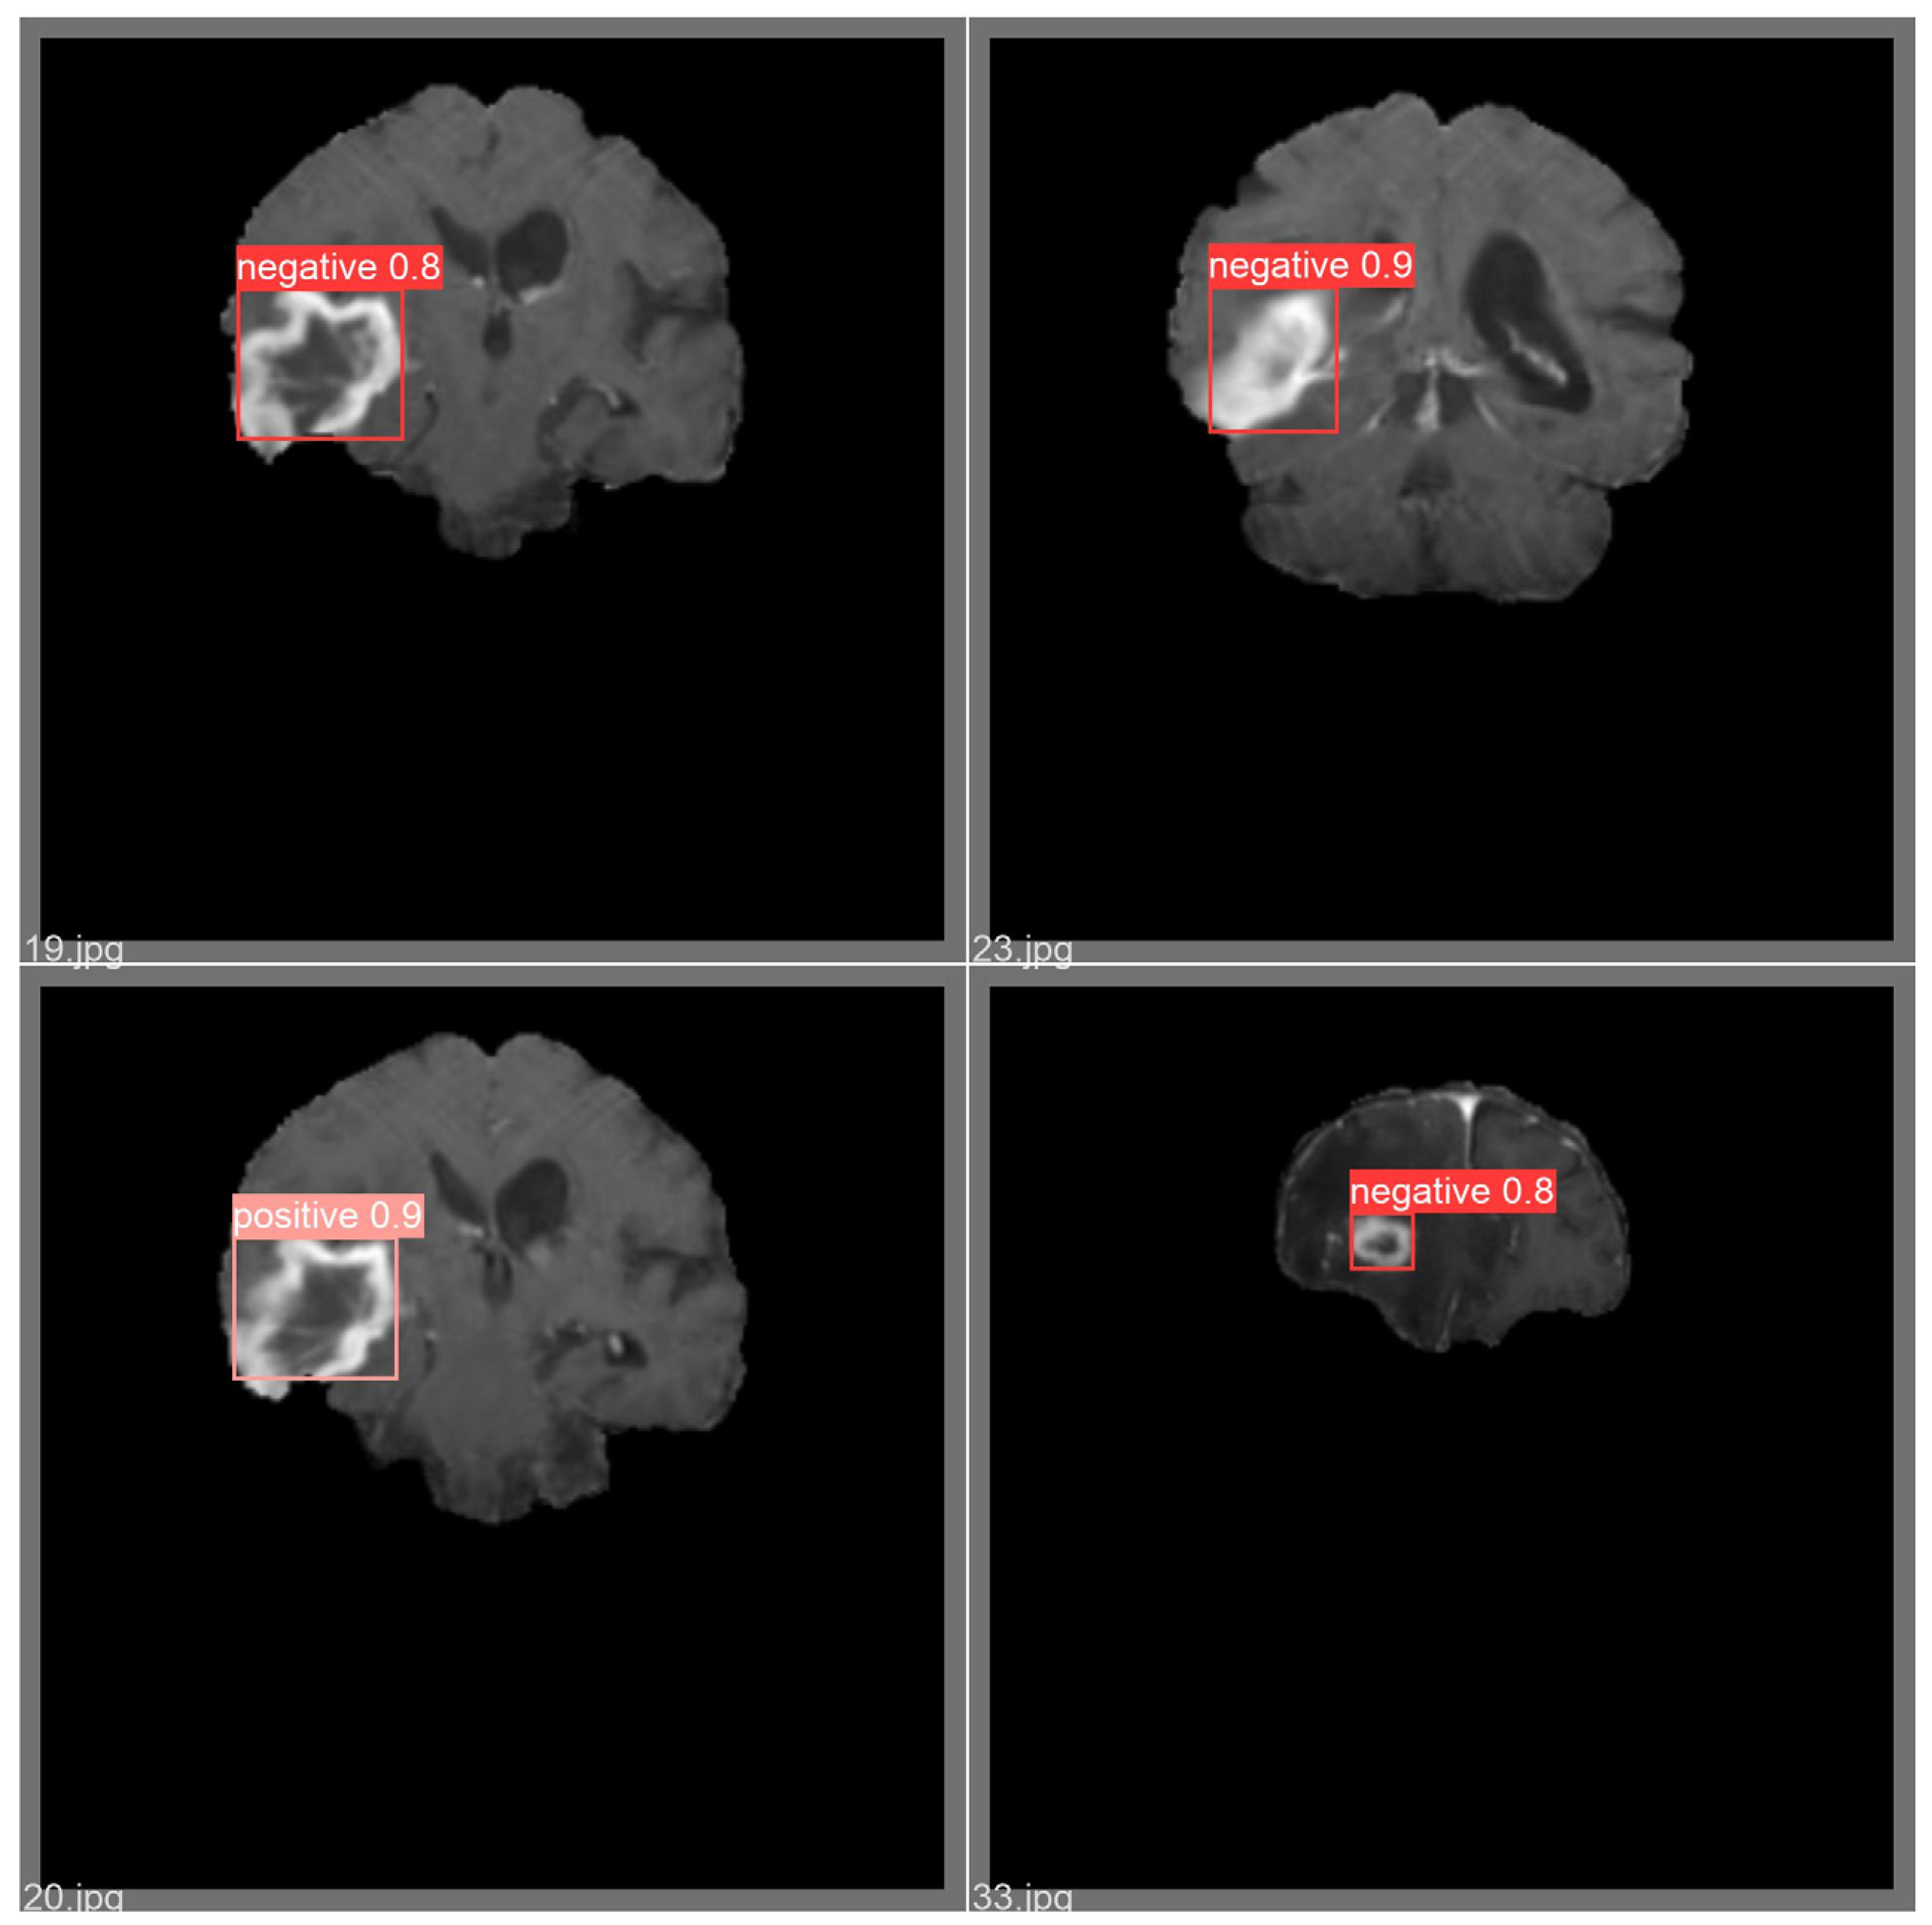

| Model | Precision | Recall | mAP |

|---|---|---|---|

| YOLOv5 | 81.9 | 83 | 87 |

| Improved YOLOv5 | 83.5 | 86 | 85.2 |